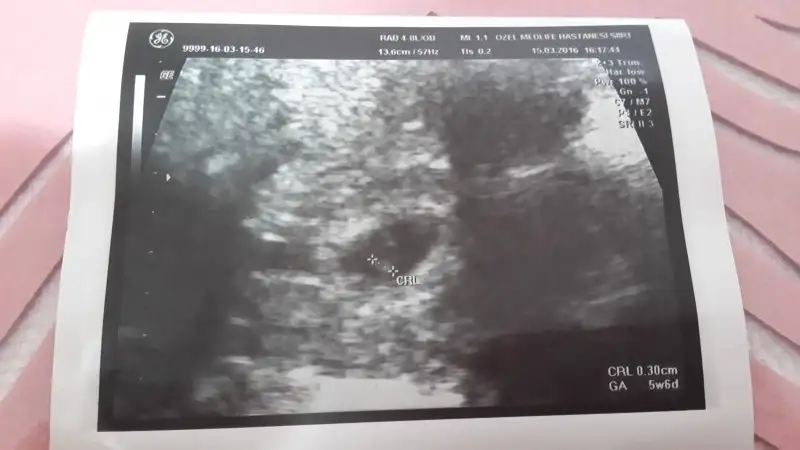

aaaa sevindim.canim gozunuz aydin benim ikizler 8+2 usg paylastim sen ne diyorsun canimcanım kıza benzettim ben bunu hem kese hem konum olarak. bi önceki ultrason varsa ona bakiyim daha küçükken. bu arada ablamında bebiş gözüktü çok şükür :) ama onunki tek çıktı ikiz değilmiş.

8+0 canim baskada varmi bilmiyorumcanım kıza benzettim ben bunu hem kese hem konum olarak. bi önceki ultrason varsa ona bakiyim daha küçükken. bu arada ablamında bebiş gözüktü çok şükür :) ama onunki tek çıktı ikiz değilmiş.

eğer karındansa erkek canım ikiside :) rabbim gönlüne göre versin.aaaa sevindim.canim gozunuz aydin benim ikizler 8+2 usg paylastim sen ne diyorsun canim

Canim kiza benzettim ben hem kese hem bebegin konumu kiza benziyor. Tabi bizimki sadece bi tahmin.Eki Görüntüle 1807457 Eki Görüntüle 1807458 burda 8 hafta 3 cü günümüz dü